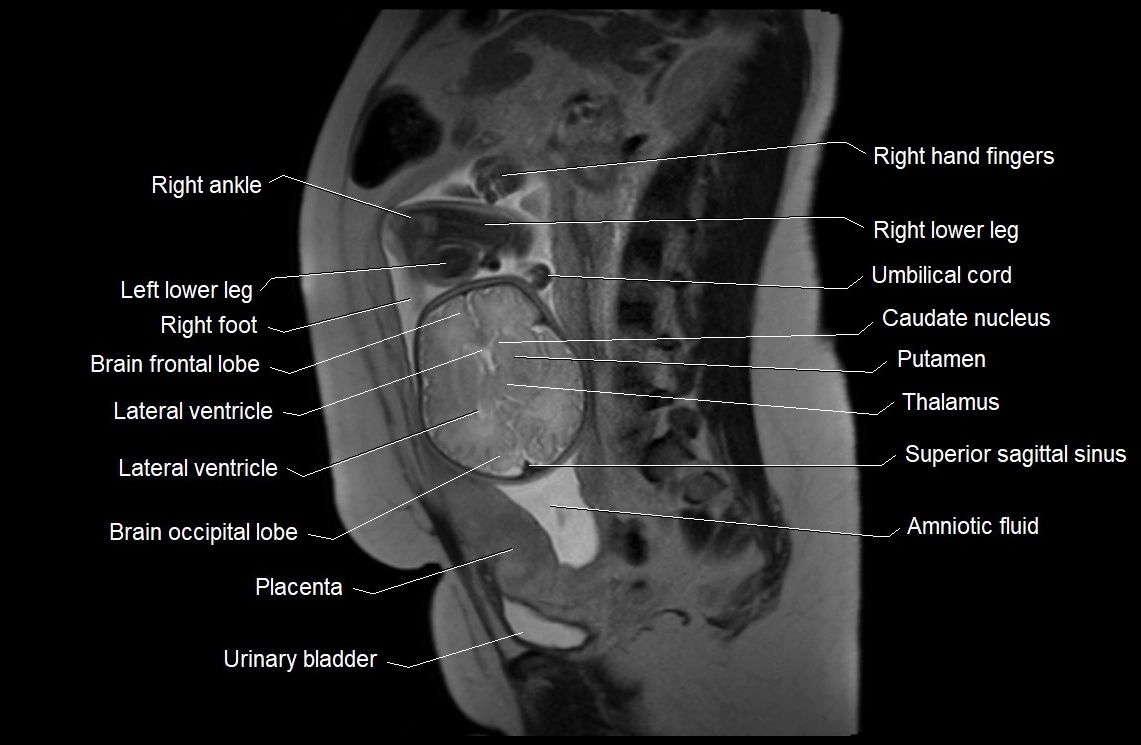

Amniotic fluid is the protective liquid surrounding the fetus within the amniotic sac. It plays an essential role in cushioning the fetus, enabling fetal movement, maintaining temperature stability, and allowing for normal lung and musculoskeletal development.

The volume and composition of amniotic fluid change throughout pregnancy. It is mainly derived from maternal plasma in early pregnancy, while in later stages, it consists largely of fetal urine, lung secretions, and transmembrane exchanges.

• Imaging relevance: MRI used for fetal visualization and assessing oligohydramnios/polyhydramnios when ultrasound is inconclusive

MRI Appearance

T2 HASTE (T2 GRE):

• Amniotic fluid shows very bright hyperintense signal

• Provides natural contrast against fetus and placenta

• Small particles (vernix) may appear as scattered hypointense foci within bright fluid

T1 GRE:

• Amniotic fluid shows low signal intensity (dark)

• Hemorrhage, infection, or proteinaceous content may cause focal or diffuse high signal intensity

MRI image

image